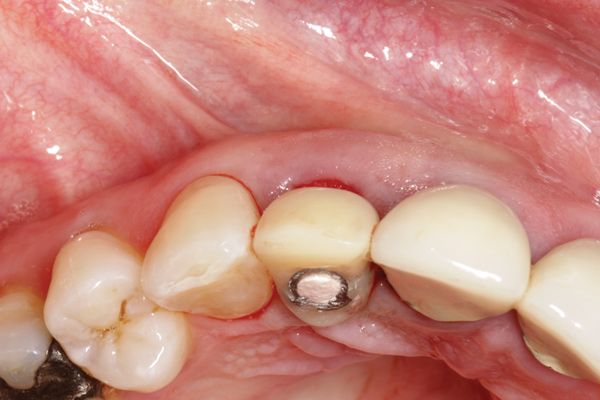

A minimum of 2 mm of facial bone thickness has been proposed as the “critical bone thickness” for the prevention of vertical height loss of the facial plate. It has been reported that when the distance of the buccal shoulder position of the implant to facial bone plate is below this critical thickness, an increased amount of facial bone resorption may be observed, which, in turn, may increase the chance of implant mucosal recession and failure (Figure 1). When the facial bone thickness is more than 2 mm from the implant buccal shoulder position, the likelihood of facial bone loss is decreased and the chance for alveolar bone stability is, therefore, increased.16

Chen and coworkers evaluated the soft-tissue and radiographic outcomes of implants placed in extraction sockets using a nonsubmerged protocol. The result showed statistically significantly higher marginal tissue recession at sites when implants were placed 1.1 mm from the inner buccal socket wall compared with implants placed 2.3 mm from the inner buccal socket wall. Six of the eight implant cases that were buccally positioned had unsatisfactory post-restorative esthetic outcomes. The authors concluded that position of the implant shoulder within the socket is a critical factor for ideal esthetic outcomes; thus, a minimum of 2 mm distance from the implant shoulder to the inner buccal shoulder wall was recommended to prevent implant marginal tissue recession.5